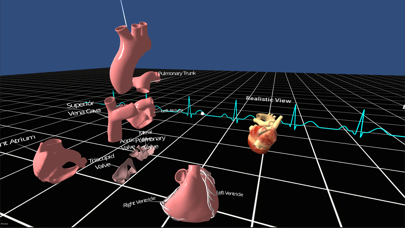

Скриншоты